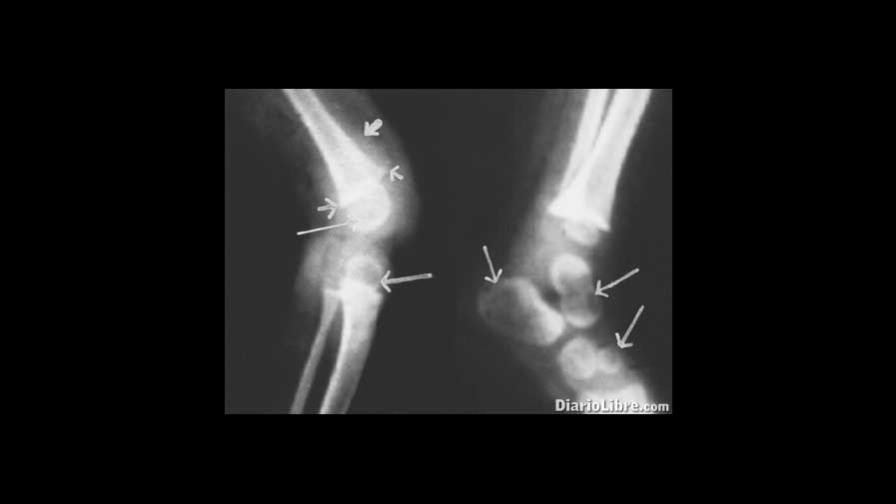

Entre los síntomas menciona, el dolor o sensibilidad en los huesos, las deformidades esqueléticas, piernas arqueadas, proyección del esternón hacia adelante (pecho de paloma), protuberancias en la caja torácica (rosario raquítico), cráneo asimétrico o de forma extraña, deformidades de la columna (curvas de la columna anormales, incluyendo escoliosis o cifosis), deformidades pélvicas, aumento de la tendencia a las fracturas óseas, deformidades dentales, retraso en la formación de los dientes, defectos en la estructura de los dientes, perforaciones en el esmalte, aumento en la incidencia de caries en los dientes (caries dentales), debilidad progresiva, disminución del tono muscular (pérdida de la fuerza muscular), calambres musculares, crecimiento deficiente, baja estatura: adultos menos de 1,52 m (5 pies) de alto